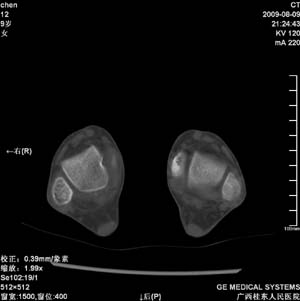

标题: PED2867:右侧内踝肿胀,骨质改变,请各位老师会诊 [打印本页]

标题: PED2867:右侧内踝肿胀,骨质改变,请各位老师会诊

九岁小朋友,近期左侧内踝疼痛,局部肿胀,平时无特殊,近期经常溜干冰

对不起,是右侧内踝肿胀

双踝关节骨质及发育未见异常。